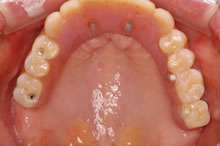

【3】治療経過写真(上アゴに仮歯が入りました。)

残りのインプラント2本も揺れていました。 CT検査の結果により、左右上奥のインプラントを支える骨が不足していました。そのため、揺れているインプラント撤去と同時に、支えるの骨を増やす特殊な手術、上顎洞底挙上術(サイナスリフト)を併用し、じっくり治療していけばインプラント治療が可能になることを説明しました。ご本人も術後の回復された後の状態がイメージでき、治療を希望され開始しました。 現在、丈夫な骨を再建する特殊な治療もインプラント6本を埋入終了し、仮歯を装着して美味しく食事をされています。 今後、下アゴにも15年以上前に入れてご自分の歯と連結されていますが揺れている経過が危ういインプラントがあるため、撤去し、再度、インプラントを予定しています。